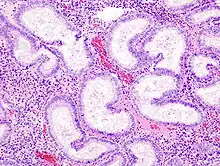

Coupe histologique de l'endomètre vue au microscope optique

L'endomètre consiste en une couche simple d'épithélium cylindrique sur un tissu conjonctif, ce dernier étant aussi appelé stroma dans la littérature scientifique. L'épaisseur de ce tissu conjonctif évolue en fonction des niveaux d'hormones. A l'intérieur de l'utérus, des glandes cylindriques simples vont de la surface de l'endomètre jusqu'à la base du tissu conjonctif, qui acheminent aussi un apport sanguin depuis les artères spiralées utérines. Chez une femme en âge de procréer, deux couches d'endomètre peuvent être distinguées. Ces deux couches sont présentes uniquement à l'intérieur de l'utérus, et non à l'intérieur des tubes utérins (anciennement appelés trompes de Fallope)[4],[5].

• La couche fonctionnelle est adjacente à la cavité utérine. Cette couche se développe à partir de cellules souches[1] à la fin des menstruations, dans la première partie du cycle menstruel. La prolifération des cellules d'endomètre, qui donne son épaississement, est provoquée par de l'œstrogène produit par les ovaires : il s'agit de la phase folliculaire du cycle menstruel. Ensuite, lors de la phase lutéale, des modifications à cette couche seront induites par du progestérone provenant du corps jaune (corpus luteum). L'endomètre est alors un environnement optimal pour l'implantation et la croissance d'un embryon. Sans embryon, cette couche se désintègre pour être évacuée lors des menstruations.